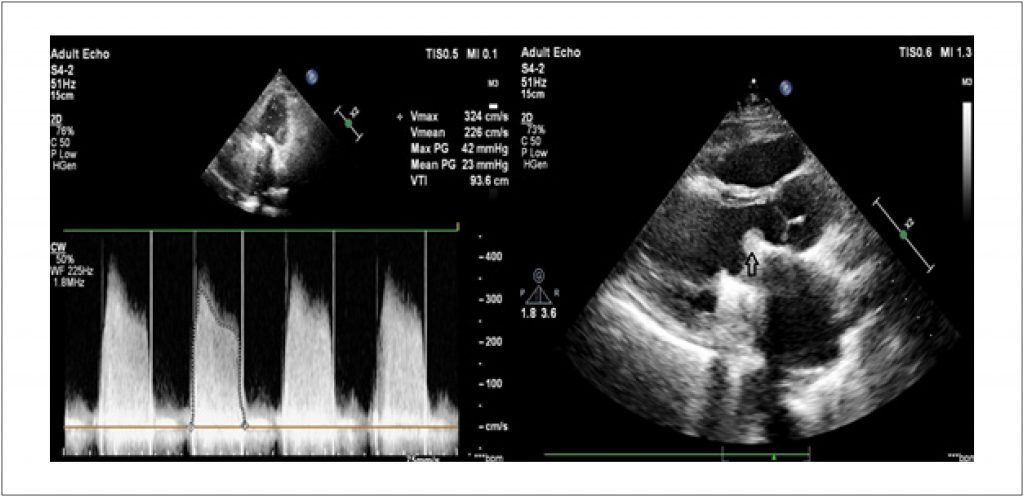

Trombose Mecânica da Válvula Mitral em Paciente com Infecção por COVID-19

Apresentamos um caso de um paciente infectado por COVID-19 com trombose da válvula mitral mecânica.